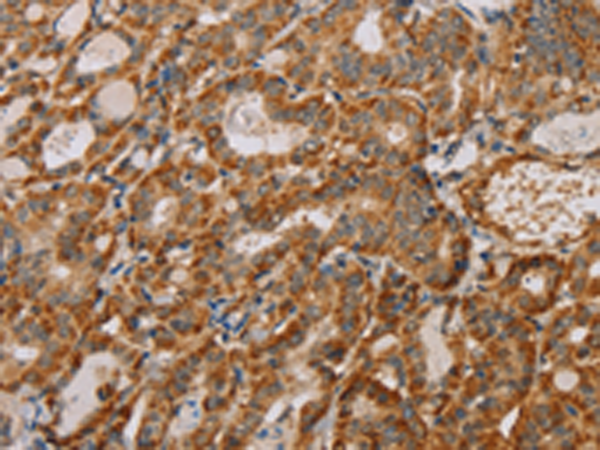

分类: 科研抗体货号: P01478别名: IMPD2; IMPDH-II应用: WB,IHC反应种属: Human, Mouse, Rat